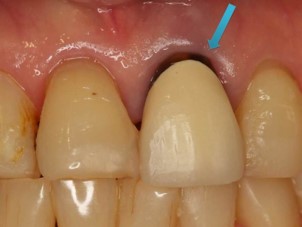

その為、金属の土台の上に白い材料を盛ることが多いのですが、それだと金属が歯茎について、ブラックマージン(歯茎が黒くなる現象)のリスクが伴います。

ですが、丈夫なジルコニアで作った場合、金属を使わないのでブラックマージンのリスクはなくなります😊